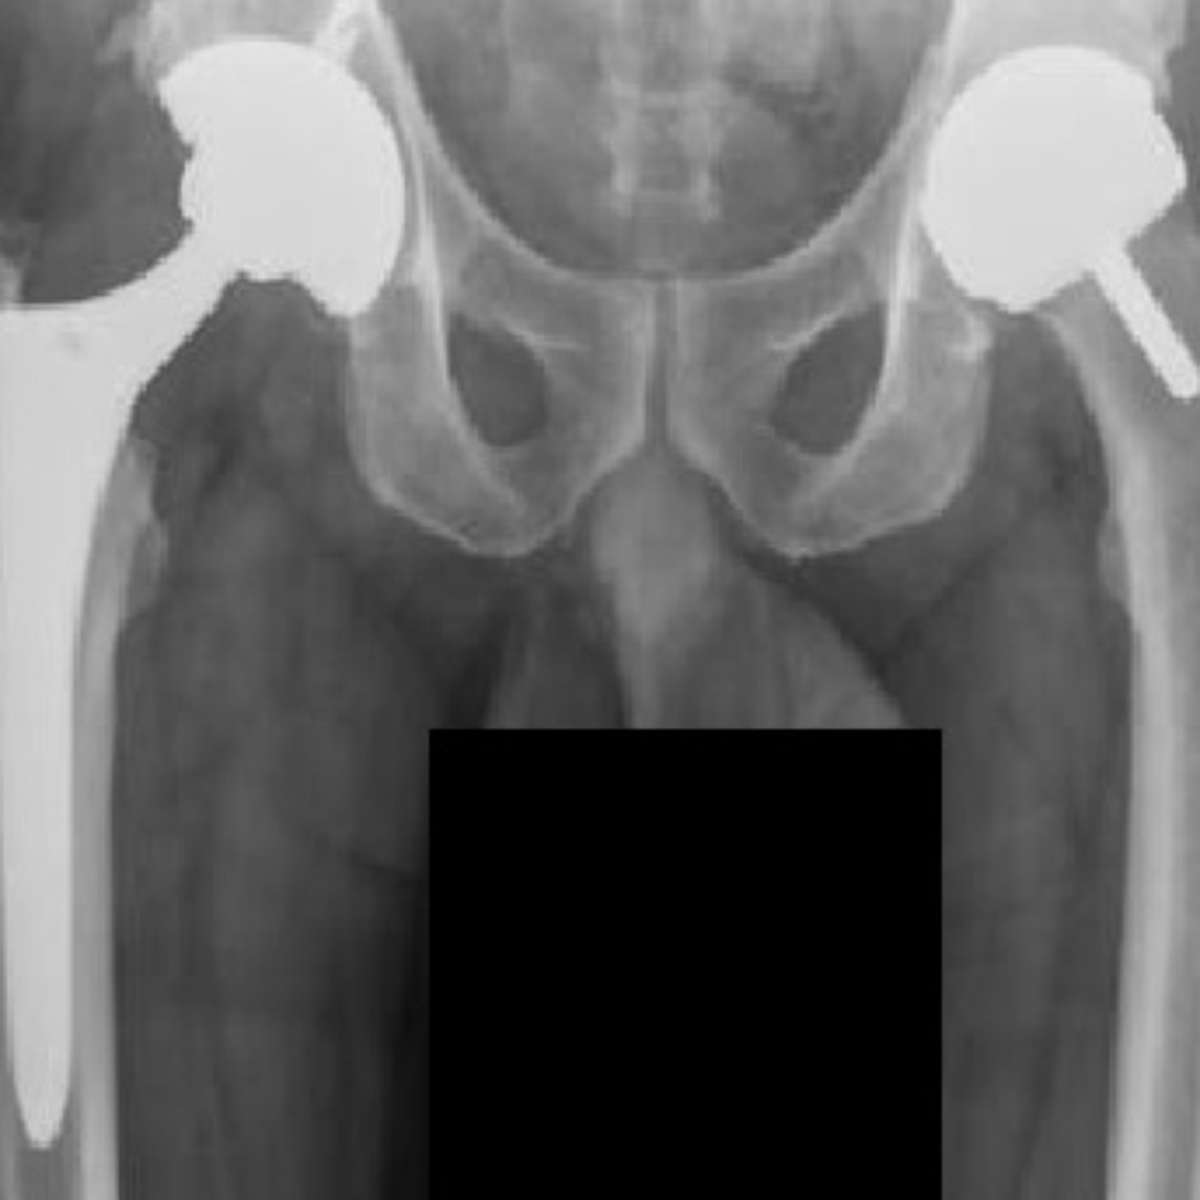

Na prática, o corpo humano é incrível na forma como se adapta. Se você tem um implante metálico, como uma prótese de quadril ou placas para fraturas, ele foi projetado para ser biocompatível. Isso significa que o material é aceito pelo seu organismo e não causa reações adversas graves. O metal usado geralmente é titânio ou ligas especiais de aço, pensados justamente para essa integração. O peso em si do implante é mínimo perto do peso do seu corpo, então a preocupação não é com o “quanto metal”, mas sim com a qualidade e a necessidade dele.

Os implantes mais comuns, como os ortopédicos, pesam gramas ou poucas centenas de gramas. Pense em uma haste de titânio para um fêmur. É um componente essencial para a sua recuperação e mobilidade. A quantidade de metal é estritamente calculada para a função que ele vai desempenhar. Não é algo que você “usa” no sentido de escolher quantidade. Ele é colocado por uma necessidade médica específica, como corrigir uma deformidade, substituir uma articulação ou estabilizar uma fratura complexa. Fica tranquila, seu médico sabe exatamente o que está fazendo!

Sabe, quando falamos de “metal no corpo”, geralmente pensamos em próteses ortopédicas, como aquelas de quadril ou joelho, ou talvez em materiais para corrigir fraturas. Esses implantes são feitos de ligas metálicas super resistentes e biocompatíveis, como titânio ou aço inoxidável de grau médico. Eles são essenciais para devolver a mobilidade e a qualidade de vida para muitas pessoas.

O peso desses implantes varia bastante. Uma prótese de quadril completa, por exemplo, pode pesar algumas centenas de gramas. Já placas e parafusos usados para fixar ossos quebrados são bem mais leves. O importante é que esses materiais são escolhidos a dedo pelo cirurgião, considerando seu tamanho, a área a ser tratada e a sua estrutura óssea. É tudo pensado para que o corpo receba bem e a função seja restaurada.

| Ligas de Cobalto-Cromo | Muito fortes e resistentes ao desgaste. Usadas em implantes ortopédicos que exigem alta resistência. | São para trabalhos pesados, como próteses de quadril. O corpo precisa se adaptar a eles. |

Quais metais são mais usados em cirurgias ortopédicas?

Titânio e ligas de aço inoxidável são os campeões em cirurgias ortopédicas. Eles são escolhidos pela resistência, leveza e por serem bem aceitos pelo corpo humano.